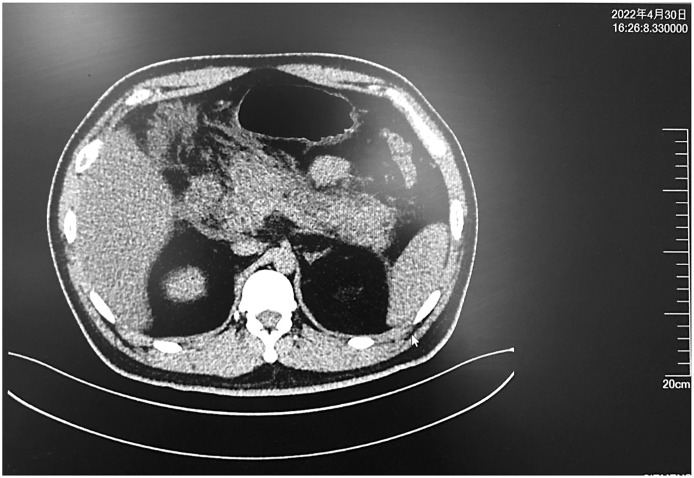

Case presentation: Here is the case history of a 31-year-old man already being treated for SAP. His condition was then complicated by massive, frequent intra-abdominal bleeding. The patient initially presented to the hospital with SAP. He was transferred to the intensive care unit for proper management. Massive intra-abdominal bleeds occurred on the 31st, 45th, and 60th days during hospitalization. The maximum blood loss was 1,500 mL. In each of the instances, digital subtraction angiography (DSA) embolization was carried out after the bleeding source had been verified. In order to manage SAP, continuous percutaneous drainage and staged pancreatic necrosectomy were undertaken for 6 months. No recurrence of intra-abdominal hemorrhage was detected. Infection of the abdominal cavity was properly controlled. The patient left the hospital in good condition.

Conclusion: Spontaneous bleeding in the abdominal cavity is a severe and life-threatening complication of SAP. This is often caused by vessel wall erosion. In such cases, DSA plays a crucial role in diagnosis and management. Besides precisely locating the bleeding source, one can perform a much-needed embolization immediately. Consequently, the disease is under total control, and the patient is much more likely to survive.